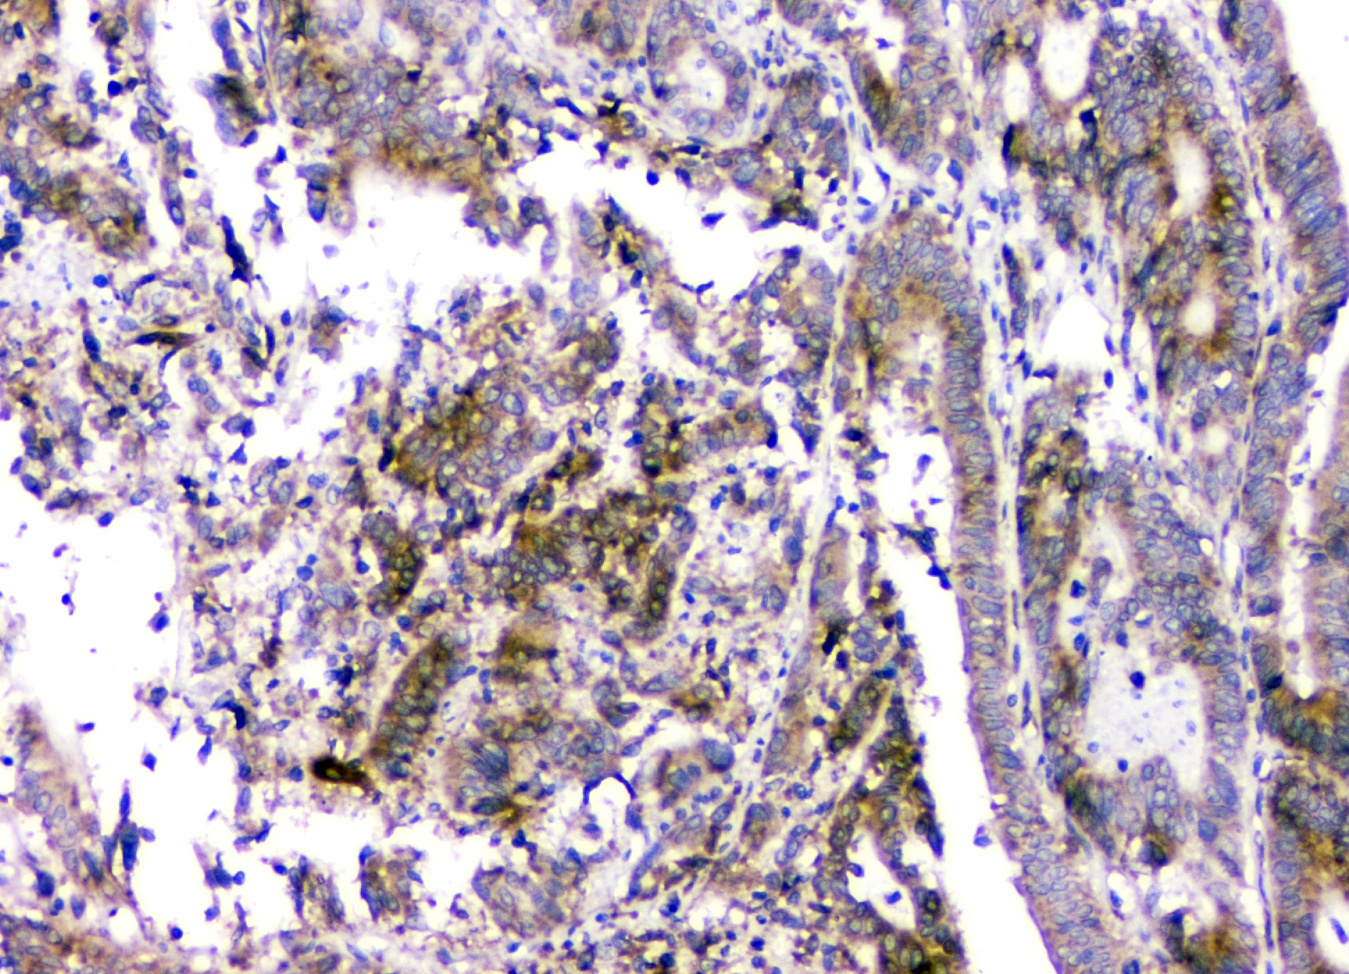

IHC analysis of RMI2 using anti-RMI2 antibody (A08685).

RMI2 was detected in a paraffin-embedded section of human intestinal cancer tissue. Biotinylated goat anti-rabbit IgG was used as secondary antibody. The tissue section was incubated with rabbit anti-RMI2 Antibody (A08685) at a dilution of 1:200 and developed using Strepavidin-Biotin-Complex (SABC) (Catalog # SA1022) with DAB (Catalog # AR1027) as the chromogen.